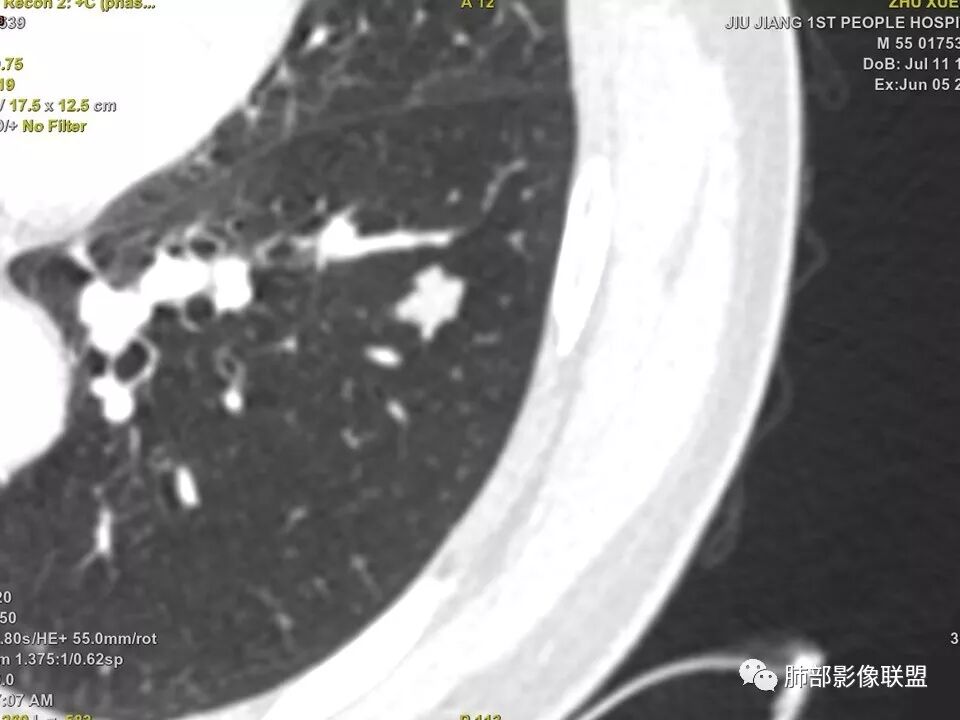

中年男性,左肺下叶不规则实性结节,有分叶及棘状凸起,支气管截断,轻度不均匀强化,考虑鳞癌,鉴别炎性肉芽肿。

左肺下叶前内基底段结节 深分叶和脐凹 表面部分膨隆 部分收缩 支气管截断 轻度强化 中央有坏死 考虑鳞癌 鉴别炎性结节

中年男性,支气管门口截断、邻近支气管未见管壁增厚,分叶明显,边缘彭隆,内见小坏死灶,周围未见GGO,考虑周围性鳞癌,鉴别炎性肉芽肿。

左肺下叶前内基底段结节,轮廓凹凸不平,局部边缘平直,密度不均,近段支气管阻塞,增强前后CT值无明显变化,考虑肉芽肿,结核?腺癌代排

左肺下叶前基底段结节,病灶边缘分叶,边缘平直,u型征,可见气管截断,增强可见病灶边缘血管,平扫ct值低,轻度强化。考虑良性病变。

实性结节,以收缩为主,强化弱,支气管截断面呈凹面,浅分叶,肉芽肿性炎

典型CT特征包括:(1)圆形或椭圆形边界清楚的病灶。(2)大小1~4cm,有轻微分叶改变。(3)较均匀的软组织影,多伴有钙化。(4)无毛刺,卫星灶及肺门或纵隔淋巴结肿大。(5)CT增强扫描无强化或轻度强化,其强化可能与软骨瘤间质中的薄壁血管或周围慢性炎症反应有关。